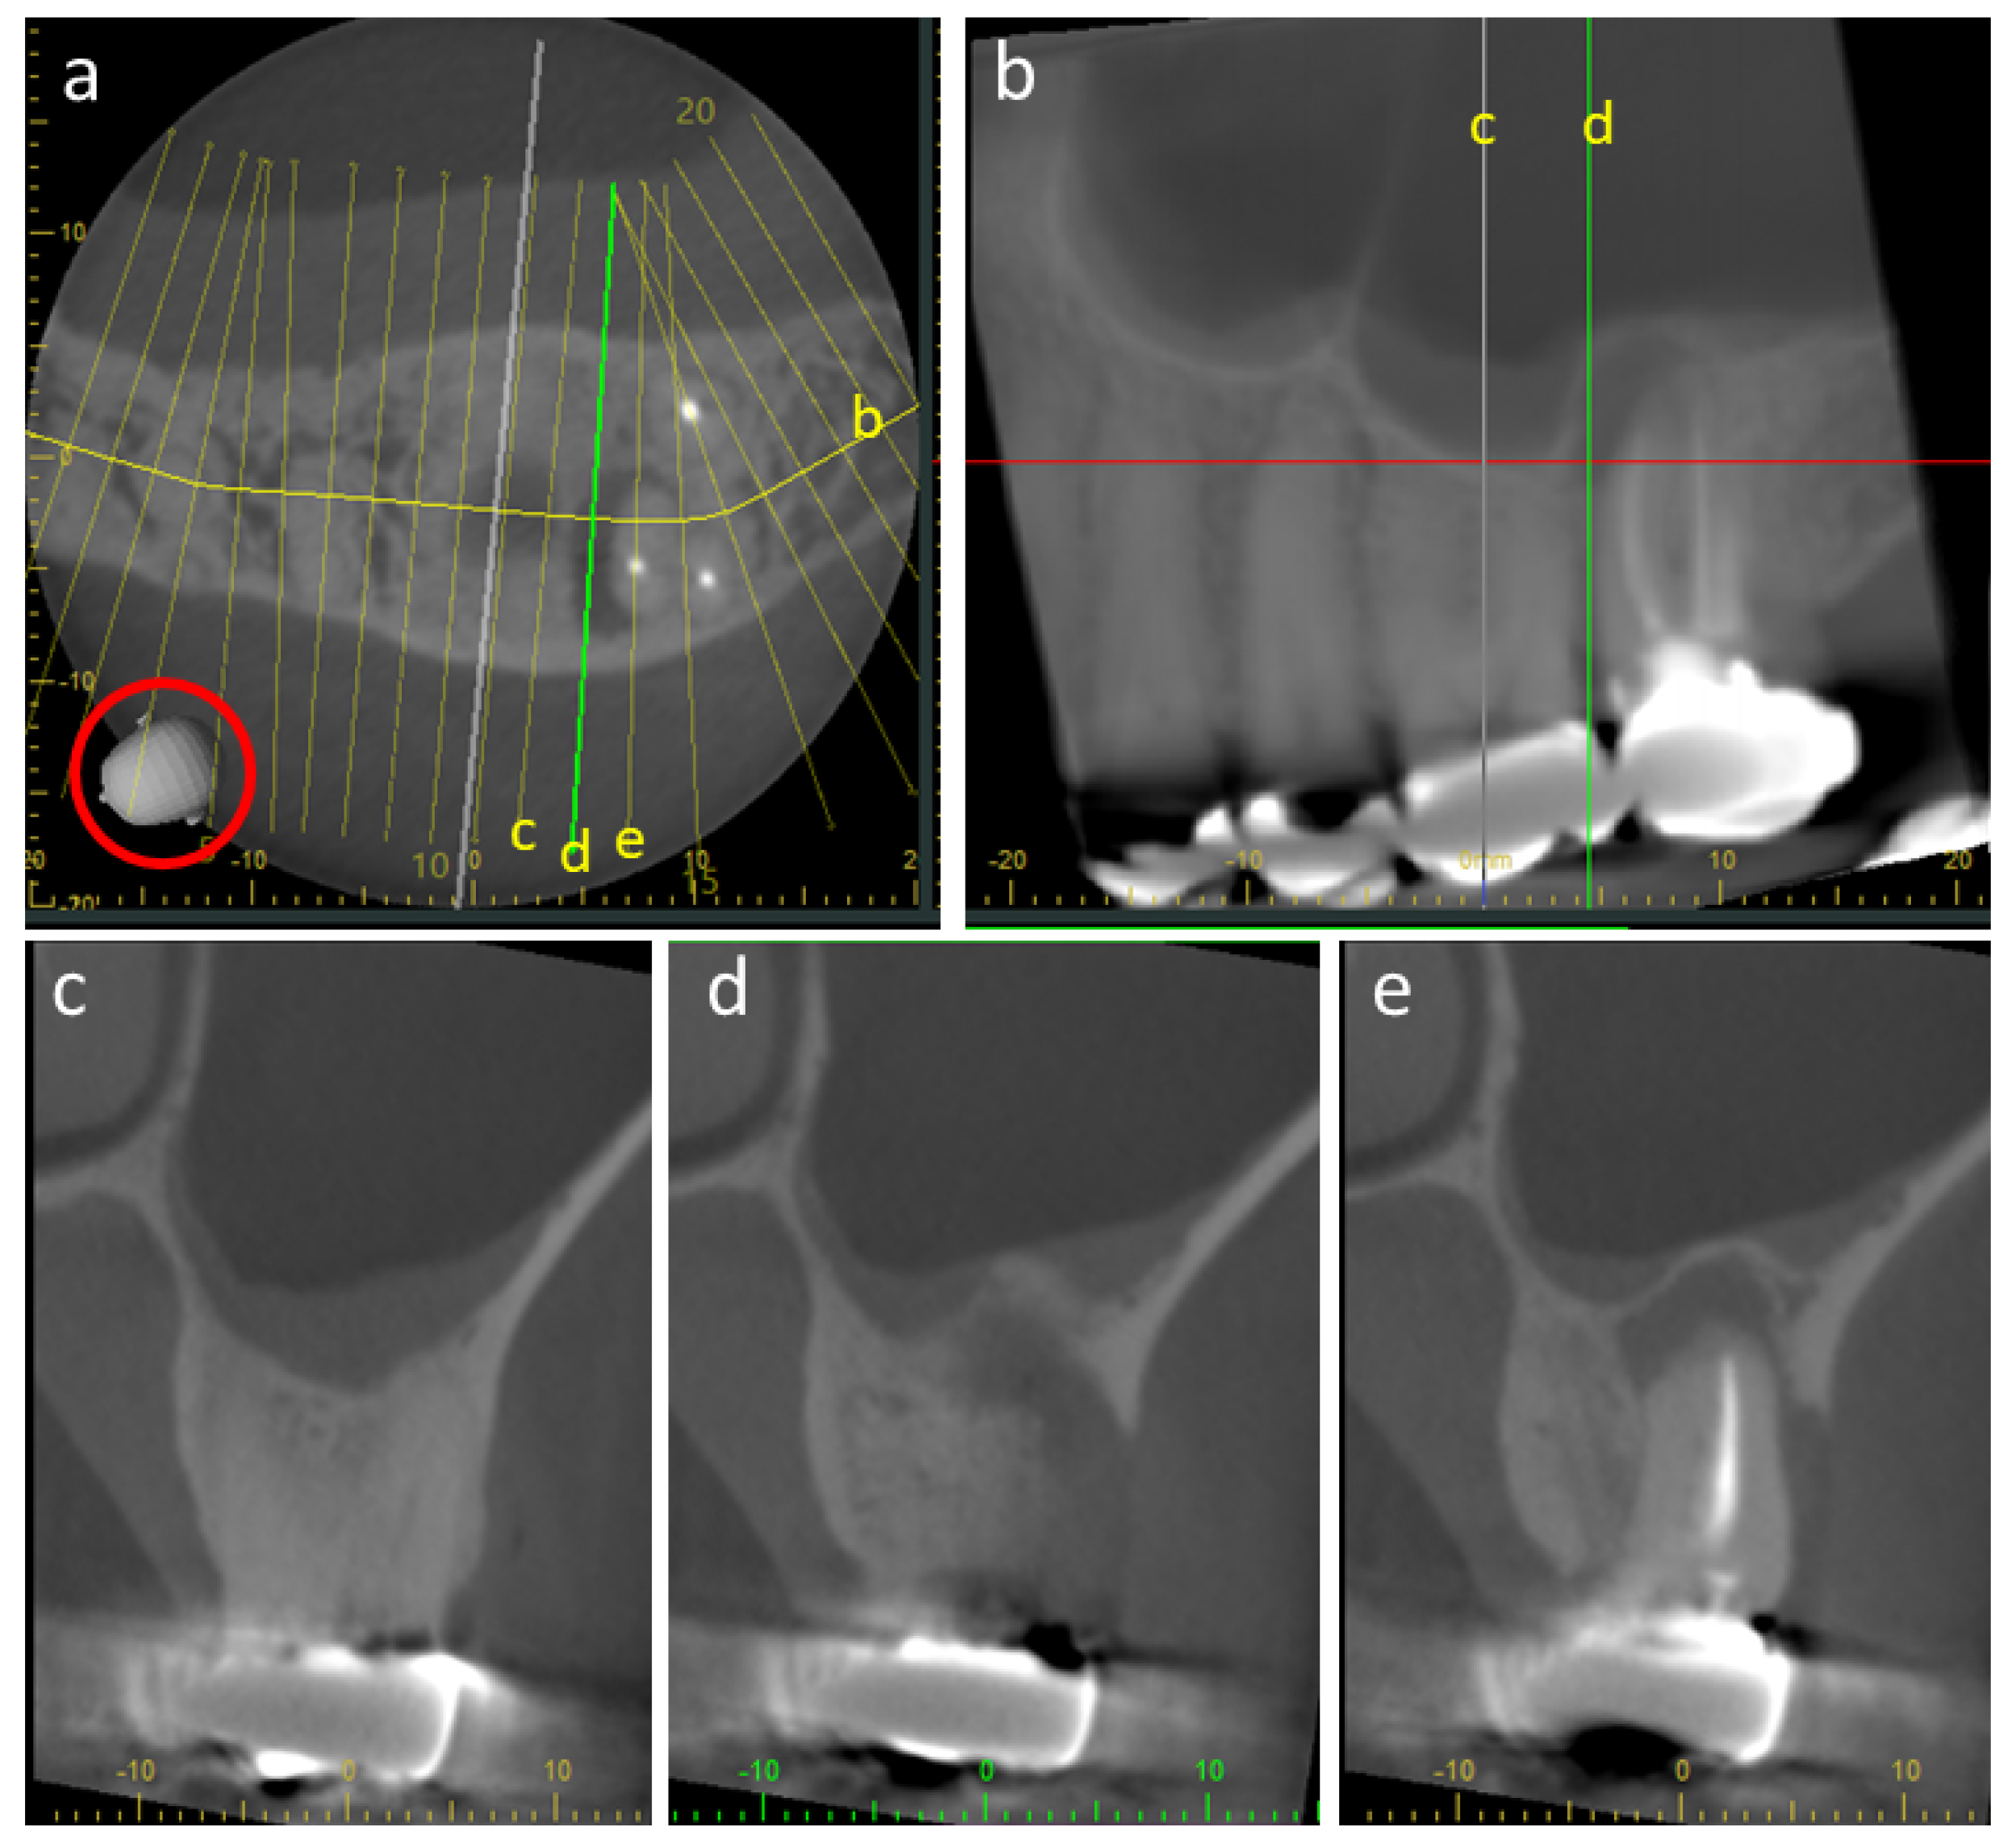

3. Cone-Beam Computed Tomography

4.2. Metal Artifacts and Use of Metal Artifact Reduction Software

- MacDonald, D.; Alebrahim, S.; Yen, E.; Aleksejuniene, J. Cone-beam computed tomographic reconstructions in the evaluation of maxillary impacted canines. Imaging Sci. Dent. 2023, 53, 145–151. [Google Scholar] [CrossRef]